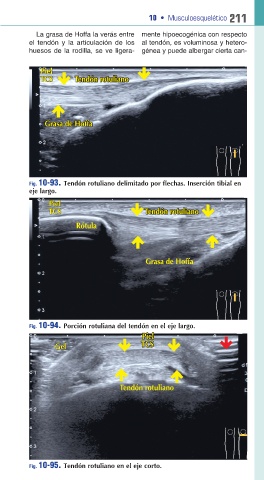

La grasa de Hoffa la verás entre mente hipoecogénica con respecto

el tendón y la articulación de los al tendón, es voluminosa y hetero

huesos de la rodilla, se ve ligera génea y puede albergar cierta can

Fig. 10-93. Tendón rotuliano delimitado por flechas. Inserción tibial en

eje largo.

Fig. 10-94. Porción rotuliana del tendón en el eje largo.

Fig. 10-95. Tendón rotuliano en el eje corto.